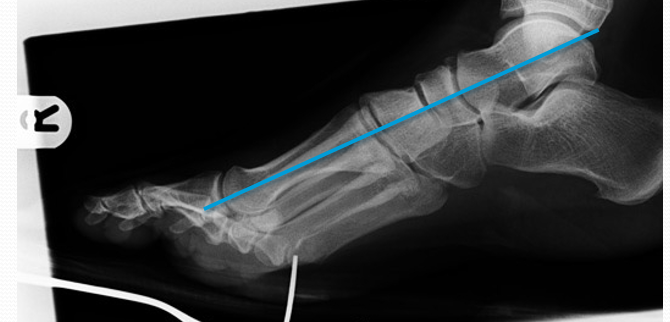

2:侧位片观察和测量第1跖骨倾斜角  第1跖骨中轴线和地面水平线的夹角。正常约为15°。此角对于术前选择手术方式意义不大,可以作为术后判断第1跖骨位置的一个参考。

第1跖骨相对于距骨关系  比较距骨颈中轴线和第1跖骨中轴线的关系。正常两线应当重叠。跖骨线位于距骨线背侧时,表示跖骨头背伸。跖骨线位于距骨线跖侧时,表示跖骨头跖屈。

第1、2跖骨关系  分别画出第1、2跖骨干背侧缘,比较两者之间的关系。正常时,两重叠或平行。在第1跖骨头背伸或跖屈时,可见两者成角。